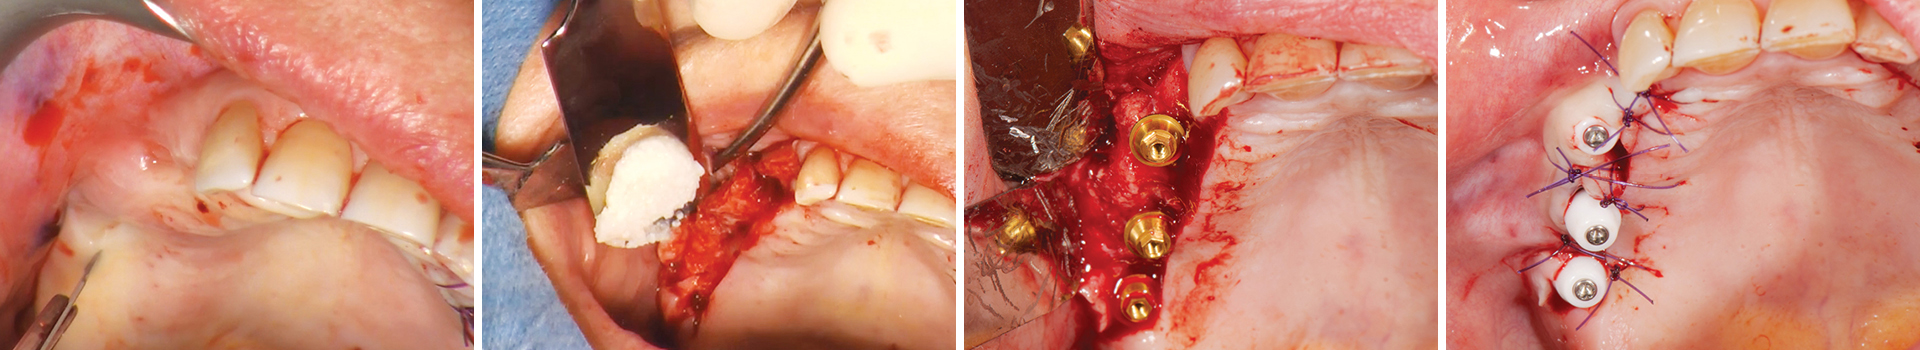

Abbildung 2

Osteotomie und Elevation der Schneiderschen Membran.

Abbildung 3

Augmentation des Sinusbodens mit OsteoBiol® GTO®.

Abbildung 4

Der Augmentationsbereich ist bereit für die Sofortimplantation.

Abbildung 5

Das OsteoBiol® GTO® im Sinus und rund um die Implantate wird kompaktiert.

Abbildung 6

Der augmentierte Sinus.